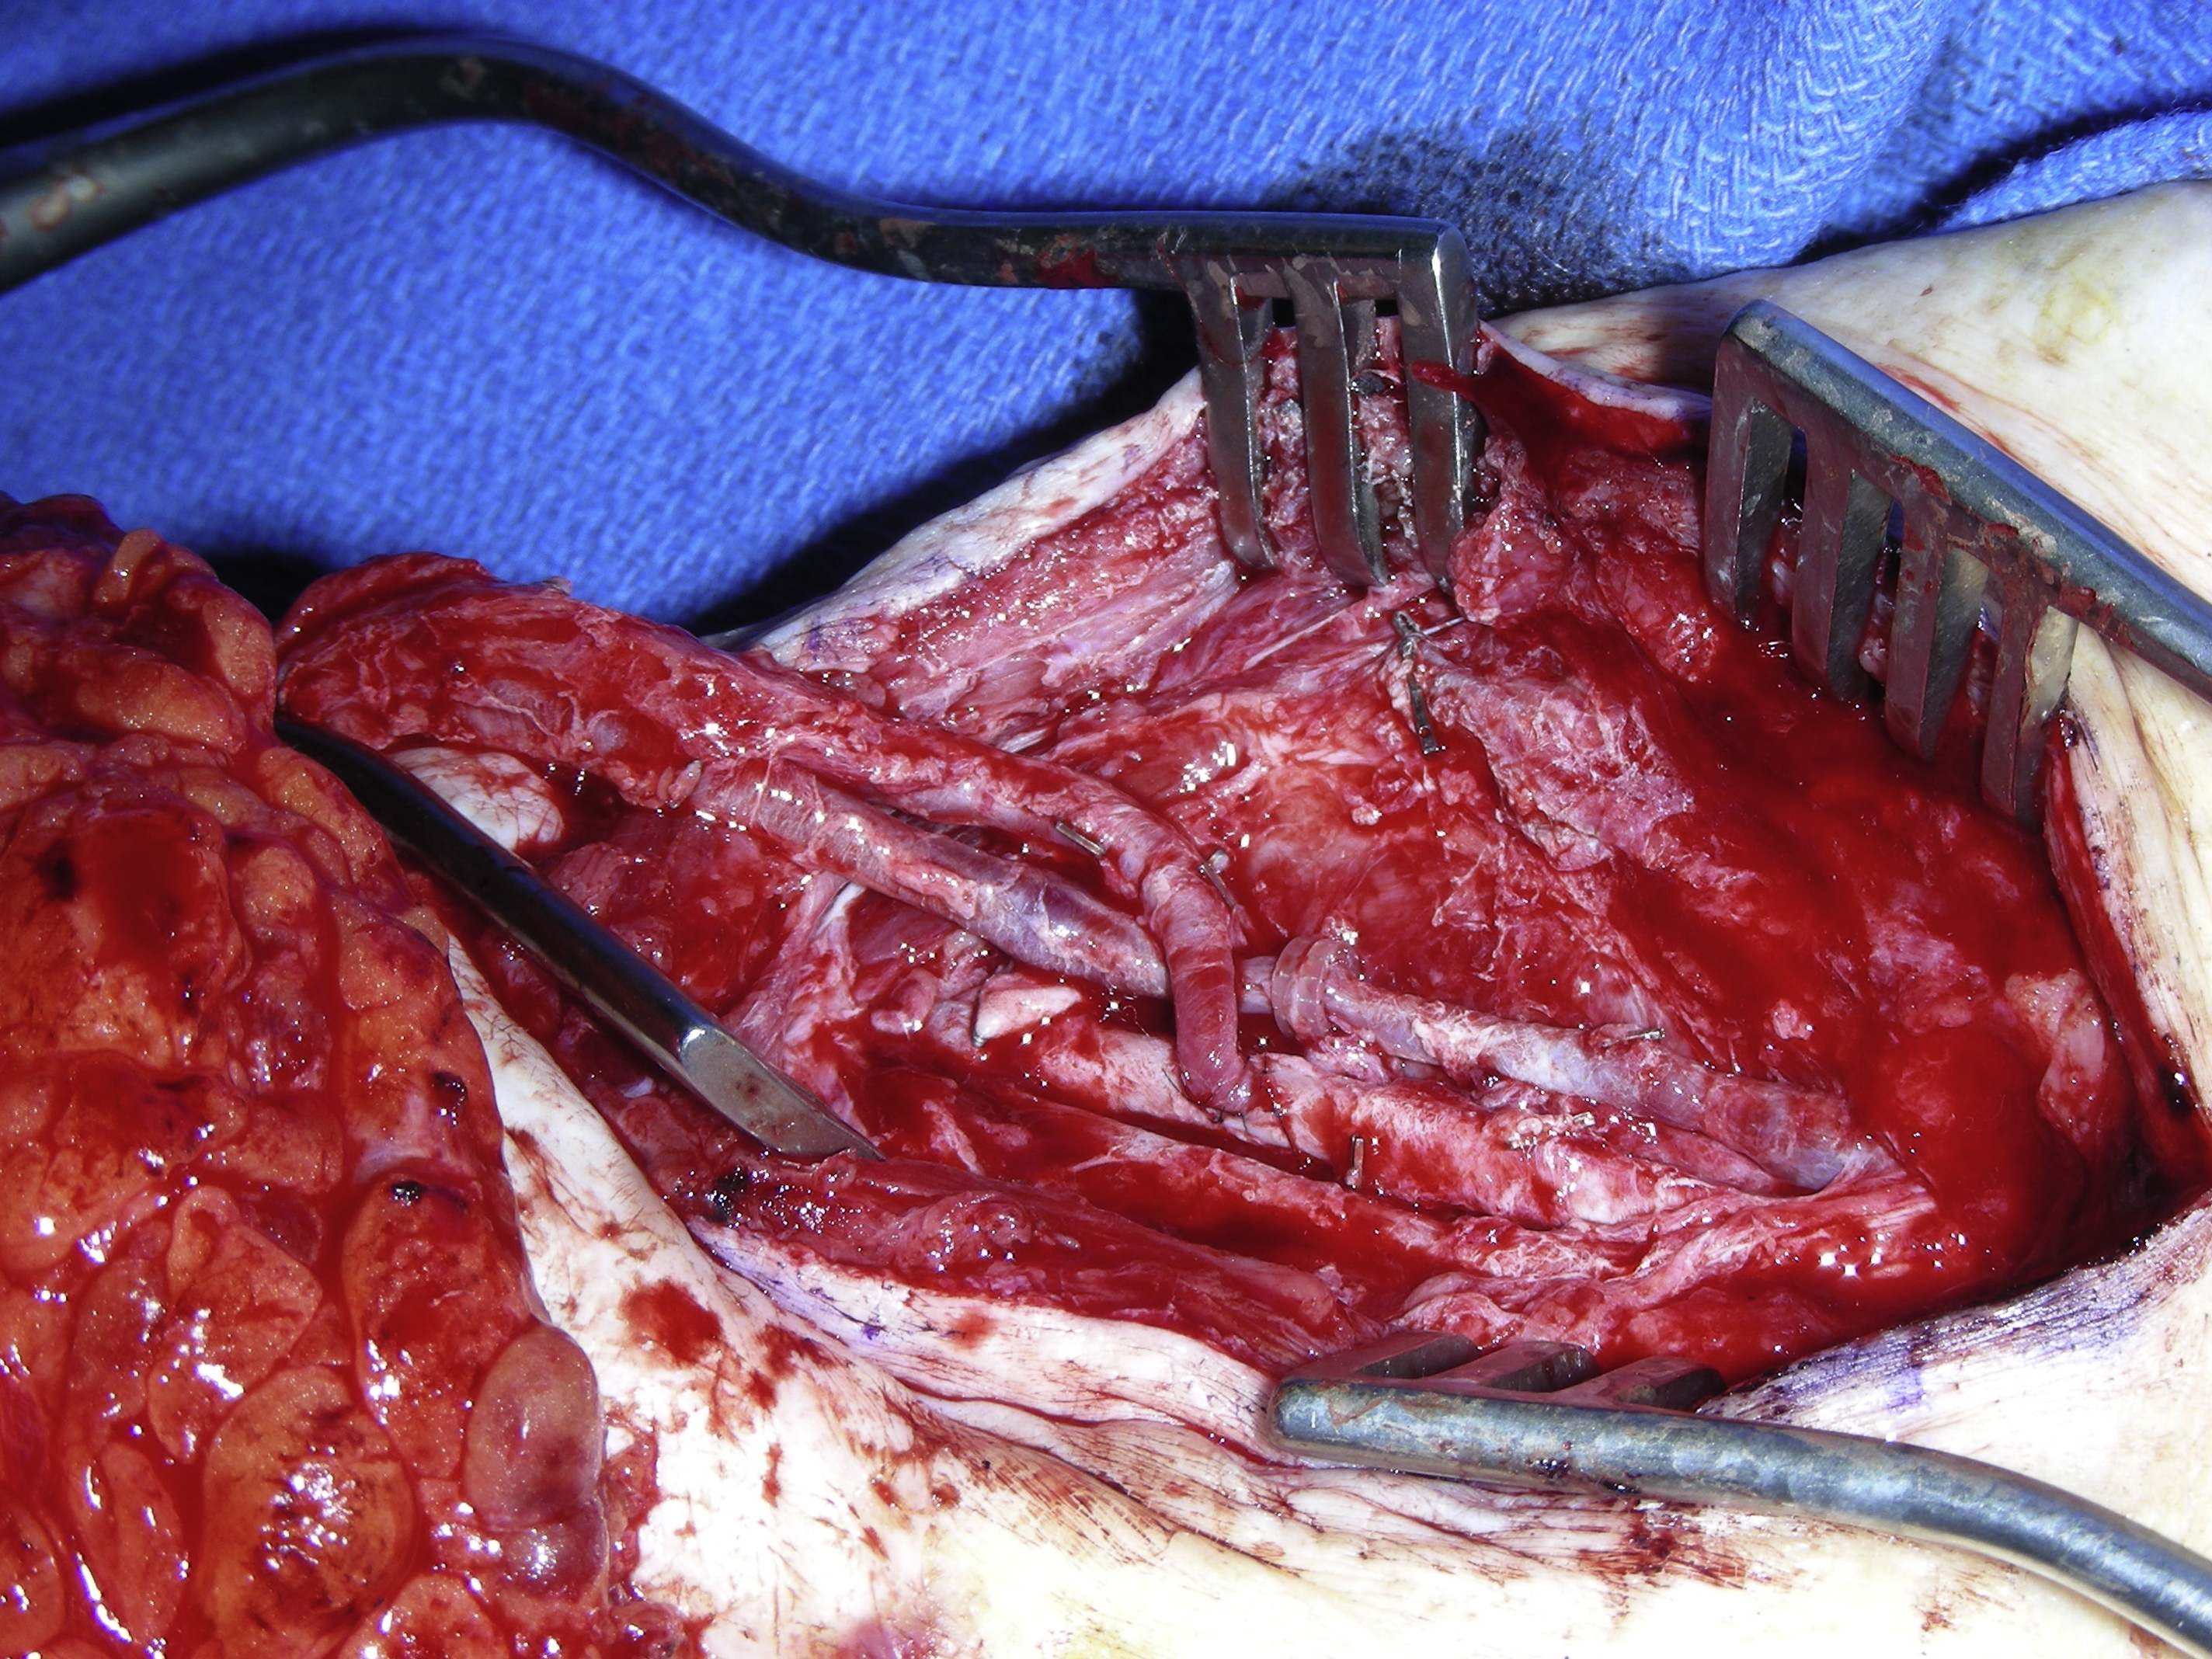

To ensure a relatively quick and easy flap dissection, the surgeon should know as much as possible about the detailed vascular anatomy of the flap before its dissection. This is particularly true for most perforator flaps. In the author’s practice, a duplex scan is routinely used for the preoperative mapping of the perforators, as well as the pedicle of the perforator flap before the flap dissection. In this way, the size and the number of the perforators that can be selected for the flap, the course of potential intramuscular dissection, and even the depth of the flap’s pedicle are evaluated. With this critical information in mind, a perforator flap, such as an ALT flap, can be elevated smoothly and safely. For an ALT flap dissection, the combination of retrograde and antegrade dissections of the pedicle can be performed for an easy flap dissection once the skin paddle of the flap is elevated ( Fig. 2 ).